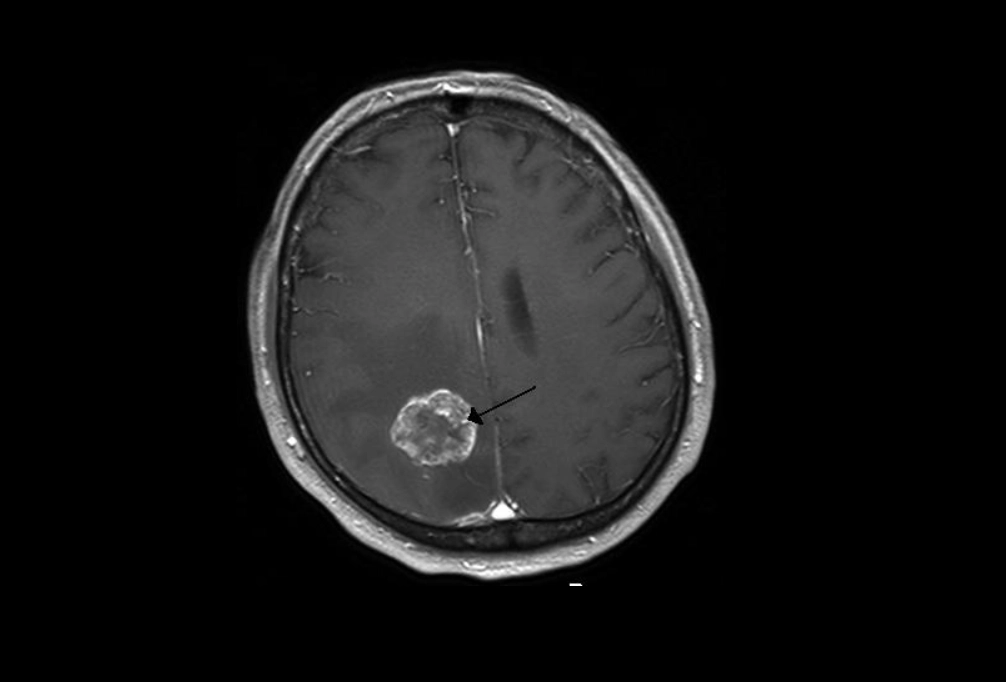

그러나 문제의 원인은 심리적인 것이 아닌 생물학적인 원인이었다. CT 검사를 받은 결과 그의 뇌에서는 7.5×8.1cm 크기의 종양이 발견됐다. 의료진은 그에게 3개월밖에 남지 않았을 수 있다며 시한부 진단을 내렸다.